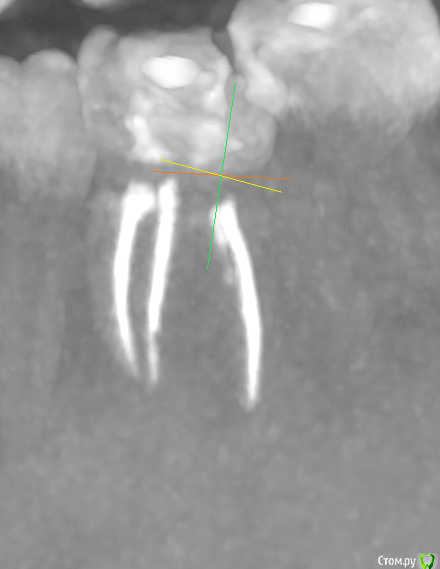

Антон999 Опубликовано 7 января, 2020 Поделиться Опубликовано 7 января, 2020 Здравствуете, имеется депульпированный нижний шестой зуб, пролеченный и с запломбированными каналами, после оценки собственных тканей зуба (коих осталось примерно 40-50% на взгляд врача) было предложено протезирование культевой вкладкой с коронкой, выбор материала культевой вкладки состоит либо из диоксида циркония либо из кобольто-хромового сплава. Из соображений биосовместимости я склоняюсь к диоксиду циркония и хочу спросить у вас совета, оправданно ли ставить разборную вкладку из ДЦ на жевательный зуб? Не будет ли это решение плохим ввиду каких-то недостатков перед КХС в плане надежности и безопасности для зуба? В кобальто-хромовом сплаве меня смущает, что исходя из некоторых источников подобные неблагородные металлы влияют на физико-химические показатели ротовой жидкости при продолжительном использовании. Или я где-то ошибаюсь и современное протезирование предполагает, что конструкция будет герметична, то есть не только вкладка, что накрывается коронкой, но и металлический каркас «шейки» металлокерамики не будет контактировать с агрессивной средой ротовой полости даже спустя несколько лет? (пару снимков из кт зуба прилагаю) Ссылка на комментарий